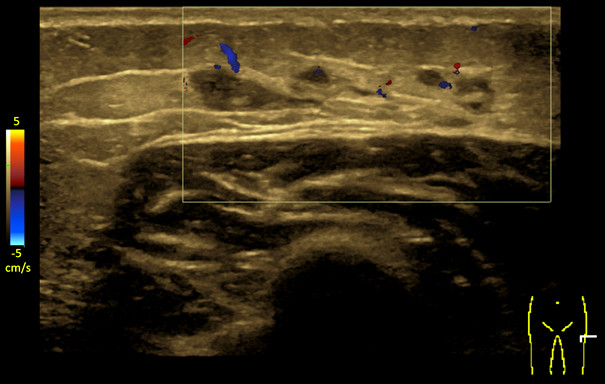

An ultrasound examination three months after the nodule was discovered showed a sharply defined, irregular lobular, multilocular cystic/anechoic lesion (approximately 3 × 0.5 cm) in subcutaneous adipose tissue, without involvement of the muscle fascia. Differential diagnoses were organised haematoma, sequelae after a focal inflammatory process, vascular malformation or other (Figure 2). The lesion remained unchanged at check-ups three and nine months later. The radiologist recommended a paediatric assessment.